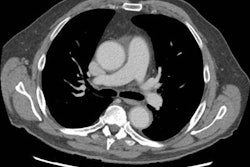

Se obtuvieron radiografías del hombro derecho del paciente. Haga clic en las imágenes siguientes para ampliarlas.